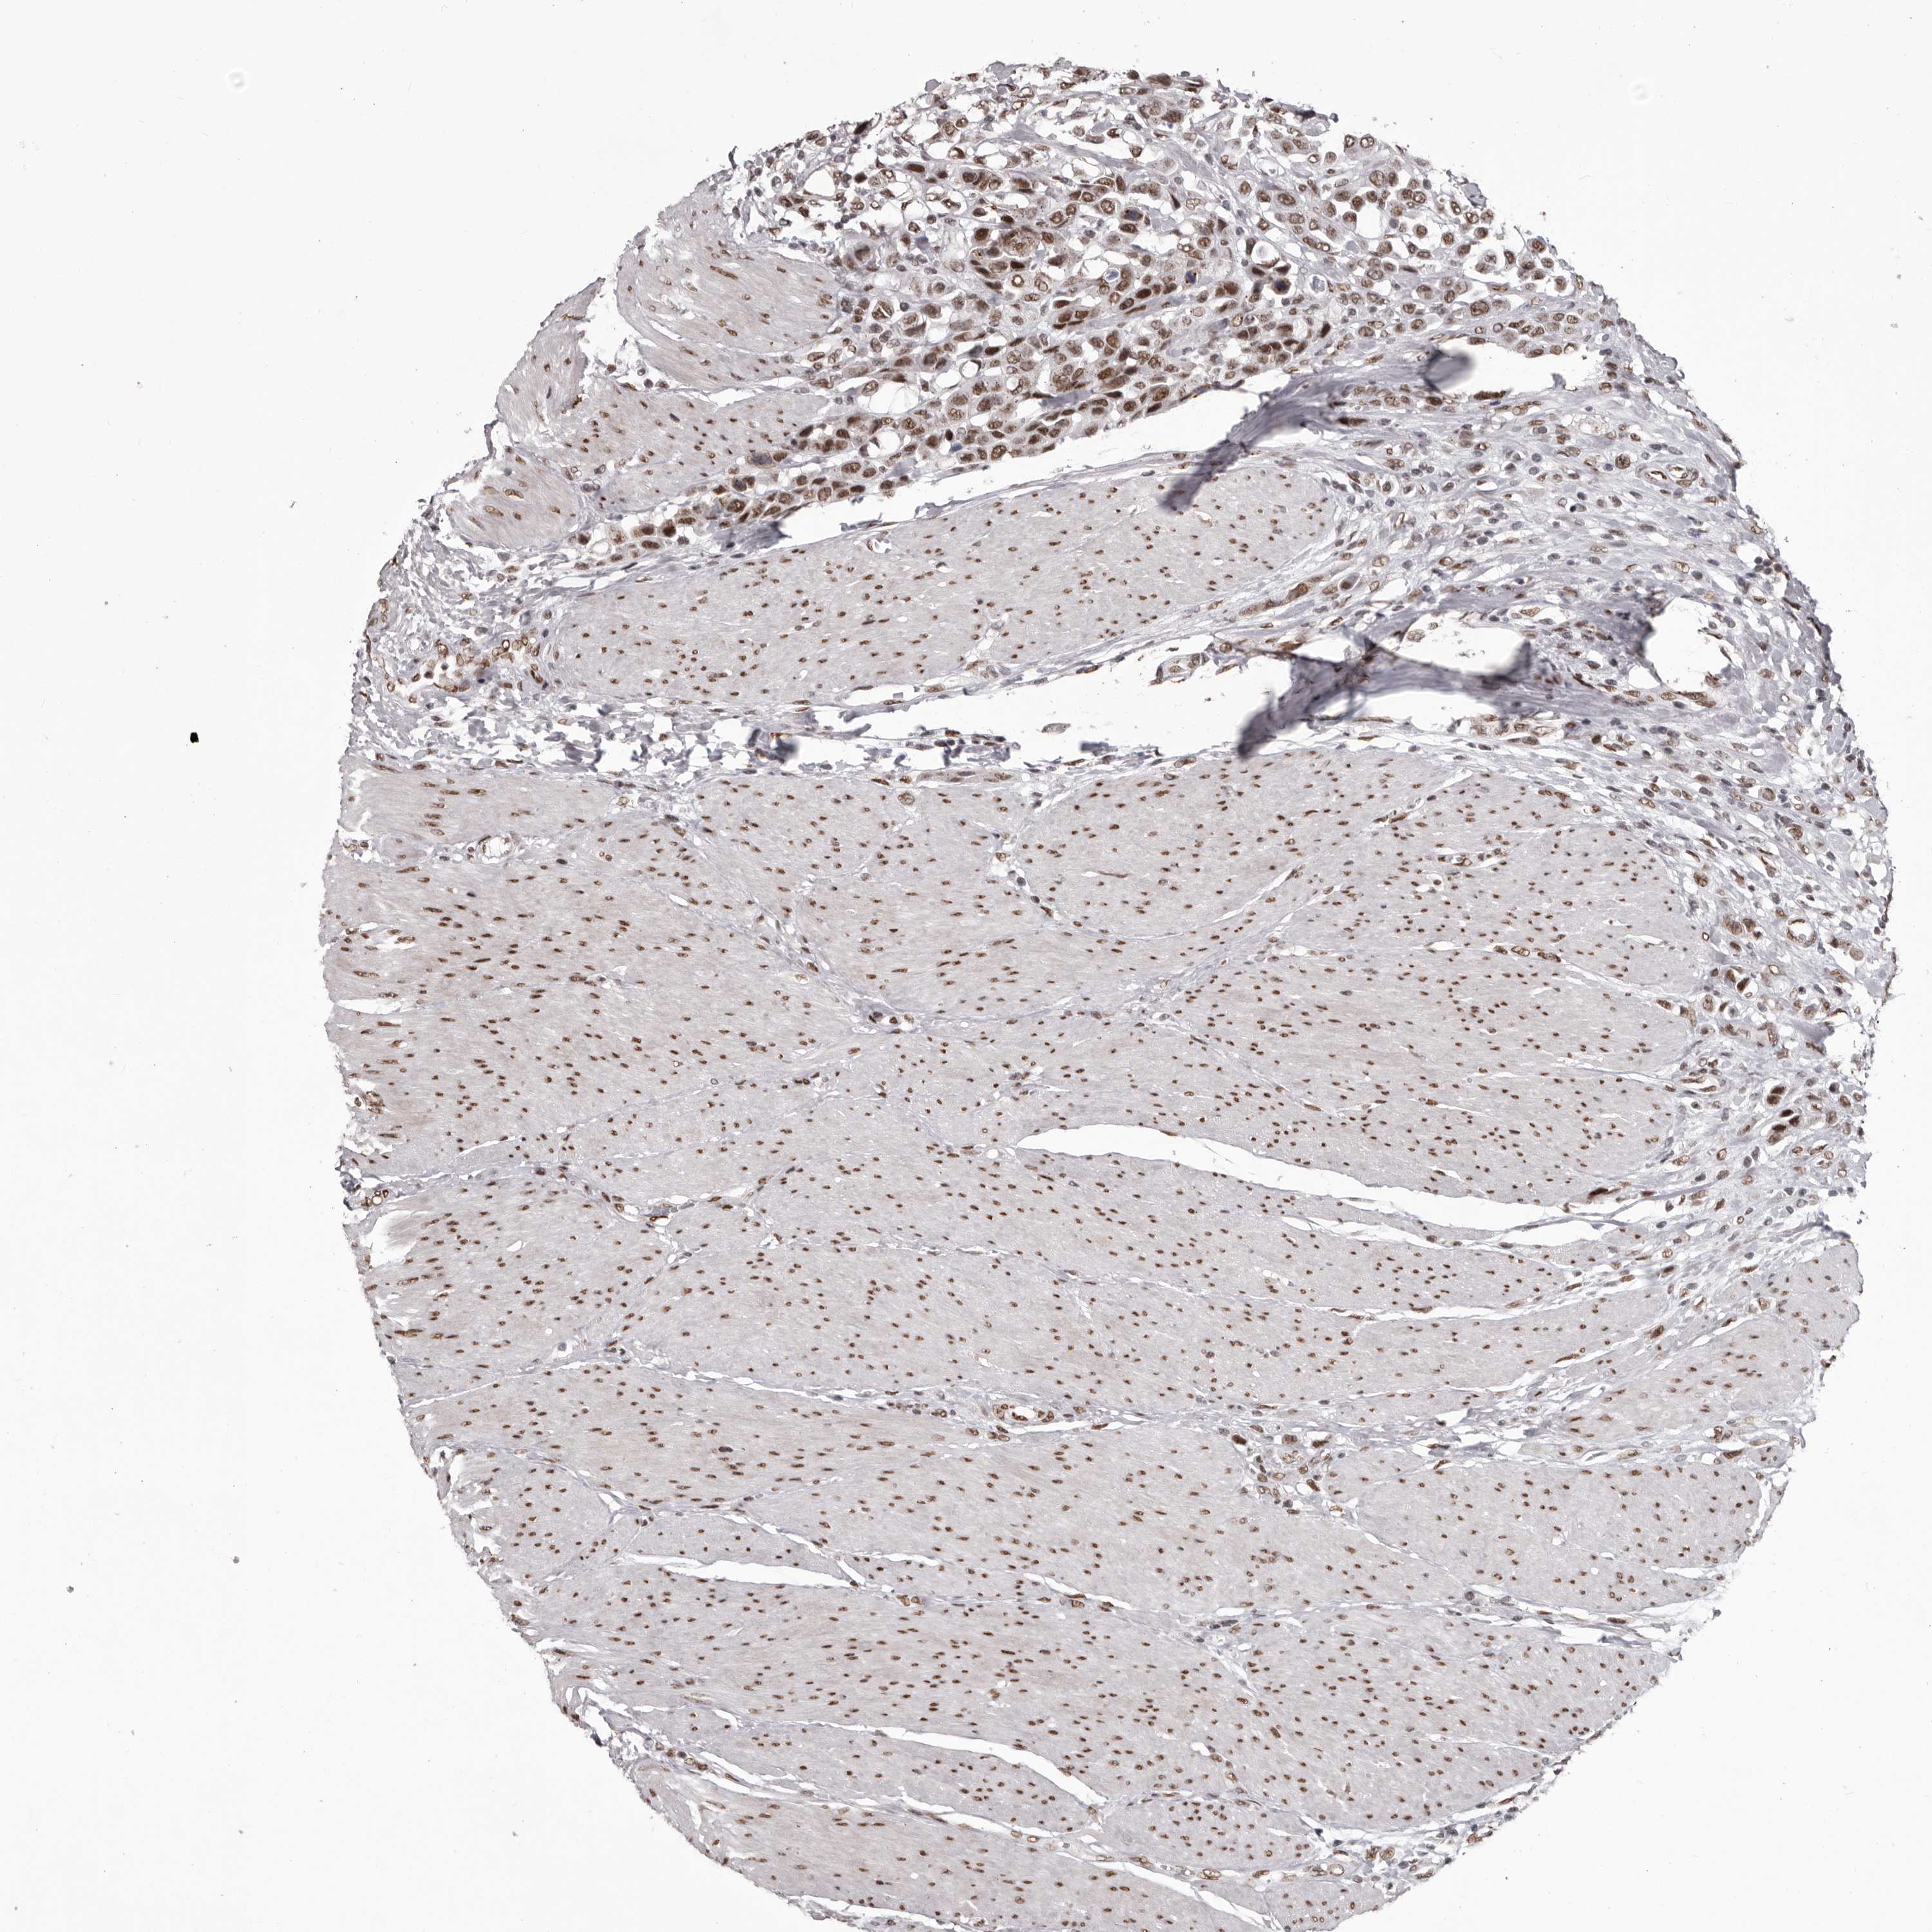

UROTHELIAL CANCER - Protein expressioni

A mouse-over function shows sample information and annotation data. Click on an image to view it in a full screen mode. Samples can be filtered based on level of antibody staining by selecting one or several of the following categories: high, medium, low and not detected. The assay and annotation is described here.

Note that samples used for immunohistochemistry by the Human Protein Atlas do not correspond to samples in the TCGA dataset.

Antibody stainingi

Antibody staining in the annotated cell types in the current human tissue is reported as not detected, low, medium, or high, based on conventional immunohistochemistry profiling in selected tissues. This score is based on the combination of the staining intensity and fraction of stained cells.

Each image is clickable and will lead to virtual microscopy that enables deeper exploration of all samples and also displays staining intensity scores, fraction scores and subcellular localization as well as patient and tissue information for each sample.

Antibody HPA019841

Antibody HPA019859

Antibody HPA029912

Staining

High

Medium

Low

Not detected

Intensity

Strong

Moderate

Weak

Negative

Quantity

>75%

75%-25%

<25%

None

Location

Nuclear

Cytoplasmic/membranous

Cytoplasmic/membranous,nuclear

Urothelial carcinoma, Low grade

Urothelial carcinoma, High grade